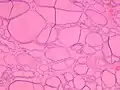

Diffuse thyroid hyperplasia typically shows variably sized follicles

The follicular linings may be thickened, with papillary projections (but lack nuclear features of papillary thyroid carcinoma) The epithelium may also be flattened by enlarged follicles.

The epithelium may also be flattened by enlarged follicles. It can show hypercellular or microfollicular areas. There is no surrounding capsule (in contrast, a thyroid follicular adenoma or carcinoma is generally encapsulated).